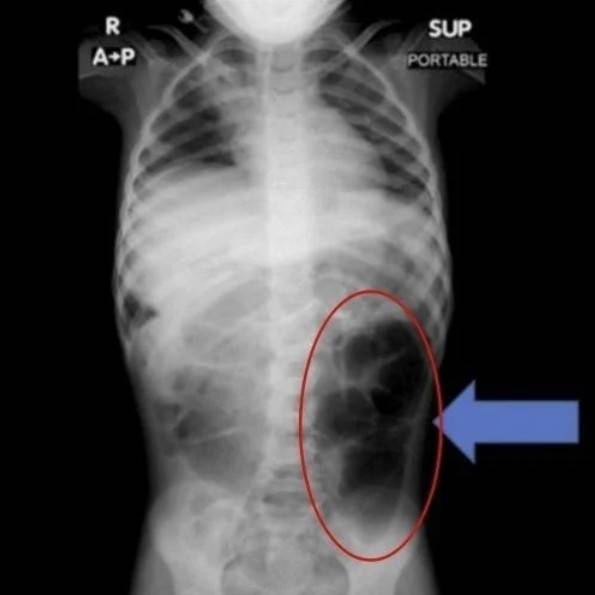

복통을 호소하던 6세 여아의 위장 안에서 예상치 못한 이물질이 발견된 사례가 학술지에 보고됐다.

이물질은 여아의 머리카락 뭉치였다.

최근 의학 전문 저널 큐레우스(Cureus)는 사우디아라비아에 거주하는 6살 여아 A양이 겪은 일을 보도했다. A양은 갑작스럽게 복통, 소화 장애 증상이 지속돼 병원을 찾았다.

의료진이 A양의 위장을 정밀 검사한 결과, 위 내부에 머리카락이 엉켜 형성된 덩어리가 발견됐다. 머리카락은 위장에만 머무르지 않고 소장까지 이어진 상태였다. 의료진은 “소아 환자에게서 반복적인 복통, 구토, 식욕 저하 등이 장기간 지속되면 위장관 내 이물질의 존재 가능성을 반드시 고려해야 한다”고 당부했다.

이처럼 머리카락을 스스로 뽑은 뒤 삼키는 행동을 ‘라푼젤 증후군’이라고 부른다. 정신질환으로 분류되고 있으며 주로 청소년기 여성에게서 발현되는 경우가 많다.

병명은 독일 지방의 설화로 알려진 동화 ‘라푼젤’에서 따왔다. 동화 속 주인공이 높은 탑에서 길게 늘어뜨린 머리카락으로 외부와 이어지는 장면처럼, 실제 질환에서도 머리카락으로 형성된 이물질이 위에서 시작해 장까지 길게 이어지는 양상을 보이기 때문이다.

라푼젤 증후군은 자기도 모르게 머리카락을 뽑아 섭취하는 습관인 발모식증, 모발섭식증 등으로 인해 위 속에 머리카락 덩어리가 쌓이고, 이 머리카락이 소장까지 침범하며 발병한다.